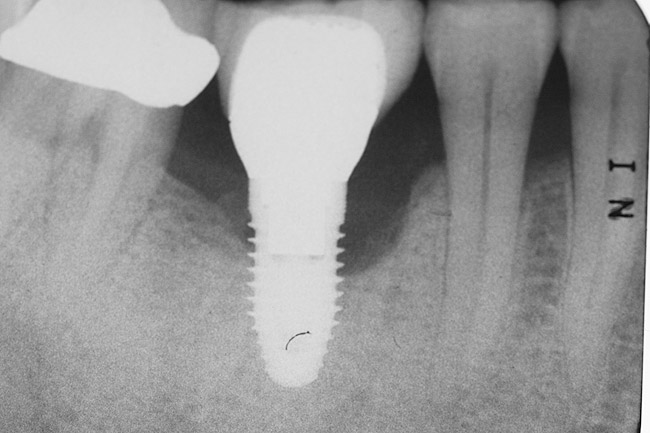

A 46-year-old man with an unremarkable medical history was referred for evaluation and treatment of the maxillary right central incisor implant. The implant, which had been placed 6 years prior, had never caused any problems until recently, when the patient noted both swelling and soreness at the site. Following 10 days of amoxicillin 500 mg tid, purulence was still present upon palpation of the tissue, and the patient was referred for consultation (Figure 6). Probing attachment loss of 10 mm on the distal aspect and 5 mm on the mesial were measured around the implant. Bone loss was advanced on the periapical radiograph at both the mesial and distal aspects of the hydroxyapatite-coated implant (Figure 7). Full-thickness facial and lingual flaps were reflected to access the implant and surrounding bone, with care taken to preserve the papilla. The defects around the implant on the mesial and distal were 1-wall, and bone loss was present on the direct facial and palatal aspects as well (Figure 8). The surface of the implant was decontaminated, followed by application of enamel matrix derivative. The lesion was filled with freeze-dried bone allograft (Figure 9). The graft-biologic was covered by a flowable polymer barrier (Figure 10). The flaps were coronally advanced and secured with monofilament sutures (Figure 11). The patient was prescribed amoxicillin with clavulanic acid and an oral rinse of 0.12% chlorhexidine during the post-operative period. The healing progressed uneventfully, achieving both a favorable soft-tissue profile and substantial bone fill, as determined radiographically. These results were stable for 7 years (Figure 12 and Figure 13).

Figure 7  Radiograph depicting loss of supporting bone around the implant.

Figure 7